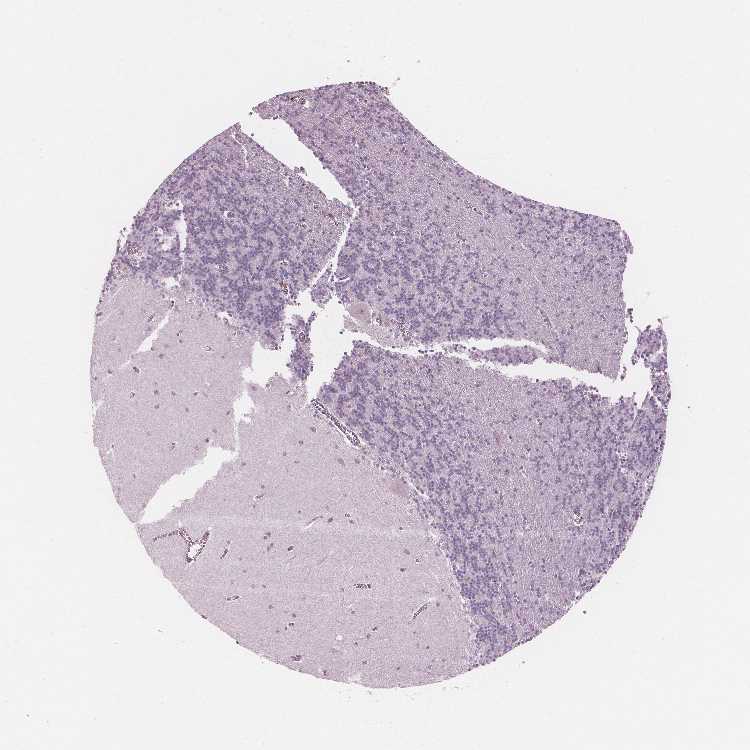

CEREBELLUM - Antibody stainingi

Antibody staining in the annotated cell types in the current human tissue is reported as not detected, low, medium, or high, based on conventional immunohistochemistry profiling in selected tissues. This score is based on the combination of the staining intensity and fraction of stained cells.

Each image is clickable and will lead to virtual microscopy that enables deeper exploration of all samples and also displays staining intensity scores, fraction scores and subcellular localization as well as patient and tissue information for each sample.

Antibody HPA066185

Purkinje cells Not detected

Cells in granular layer Not detected

Cells in molecular layer Not detected